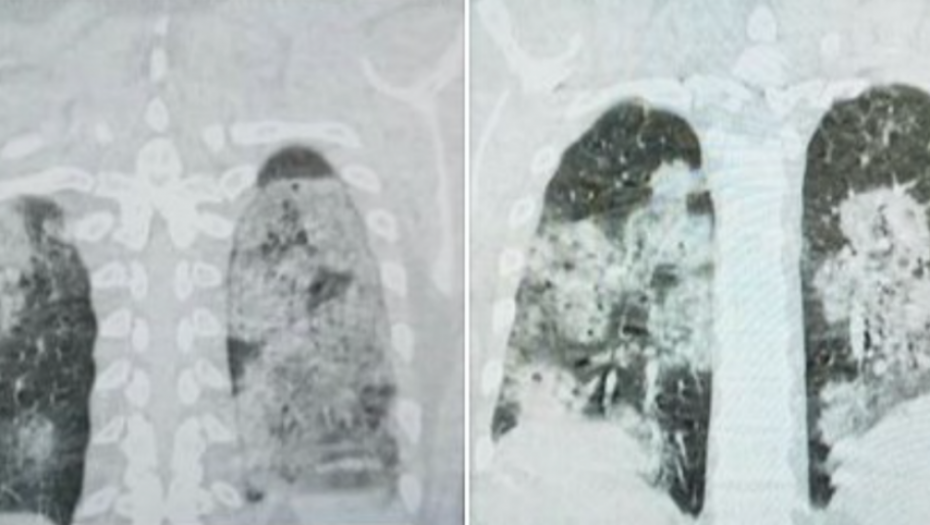

Sarajevski doktor Dragan Stevanović objavio je na Fejsbuku snimke pluća jednog od hospitalizovanih pacijenata koji je završio na kovid odeljenju.

On je objasnio da se radi o mladom, do tada zdravom čoveku koji je nepušač, a čija su pluća vidno stradala usled infekcije korona virusom.

– Za one koji ne znaju, zdrav je crni deo pluća – objavio je dr Stevanović.